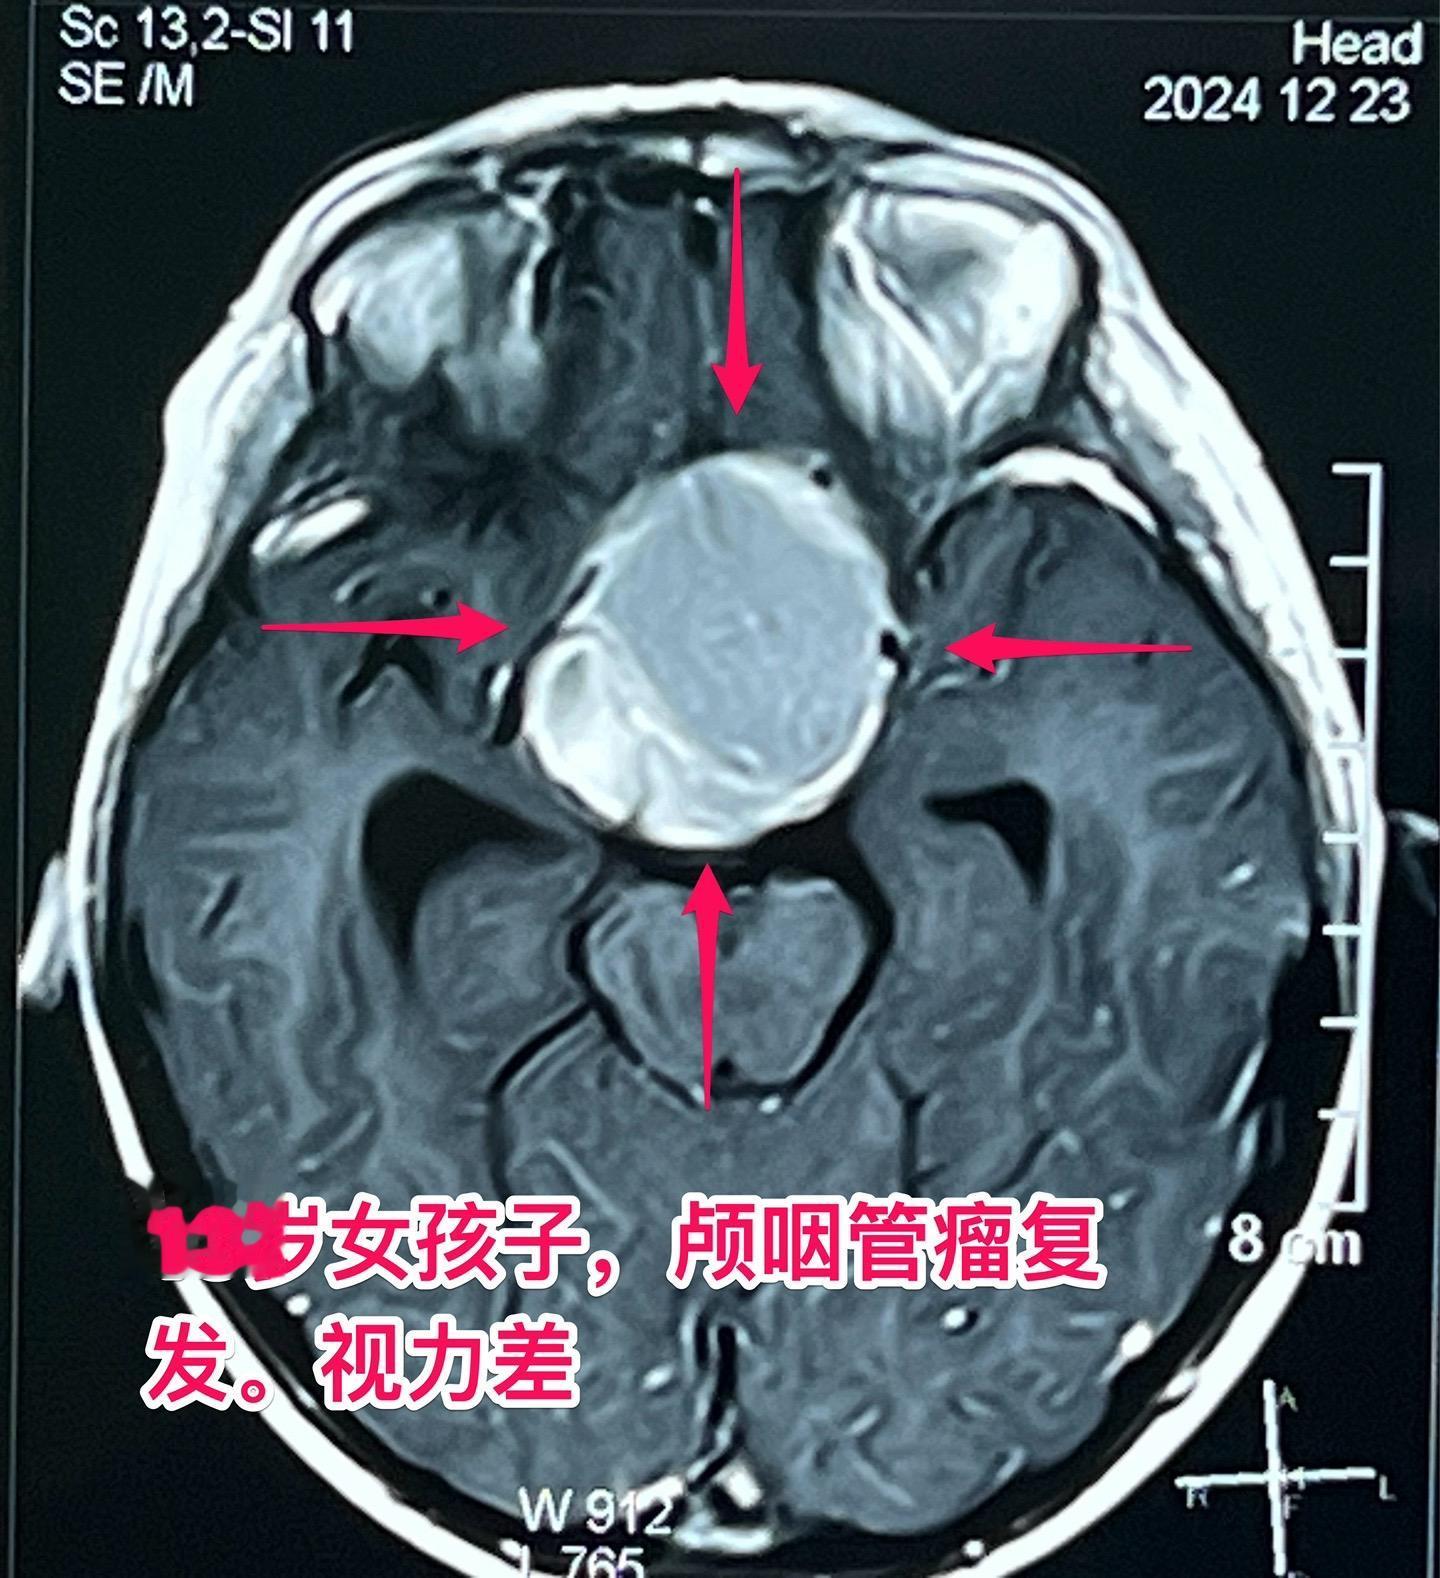

颅咽管瘤两次复发,右眼失明、左眼快失明了。13岁女孩子,因颅咽管瘤之前做过两次开颅手术。肿瘤又复发了,体积很大,垂体窝显著扩大,见图。 12月27日作了手术,将肿瘤完全切除。 这是第三次手术,手术前家长很担心左眼仅有的光感视力会不会变成全盲?会不会出现脑脊液鼻漏? 手术后患者很快就清醒了,左眼视力保住了,也没有脑脊液鼻漏出现。希望肿瘤不再复发。